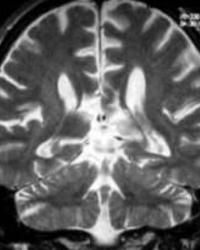

藉由核磁共振或是電腦斷層等方式來做判斷是否有出現胼胝體發育不全。

典型較嚴重的胼胝體發育不全,CT診斷不難,但對輕度或中度發育不良,有時由於層厚較厚或間隔過大,橫軸位掃描,易於漏診。對有神經運動和智力障礙,疑有胼胝體發育不全者,掃描時應在Ⅲ室和側室水平將層厚減薄到3-5mm連續掃描。較大的兒童或成年亦可用8-10mm層厚,但如有懷疑,仍需減薄到3-5mm。冠狀位有利於判斷Ⅲ室的位置。重建或直接矢狀位,更易顯示胼胝體全貌,一般不用增強掃描,但可提供另外有用信息。